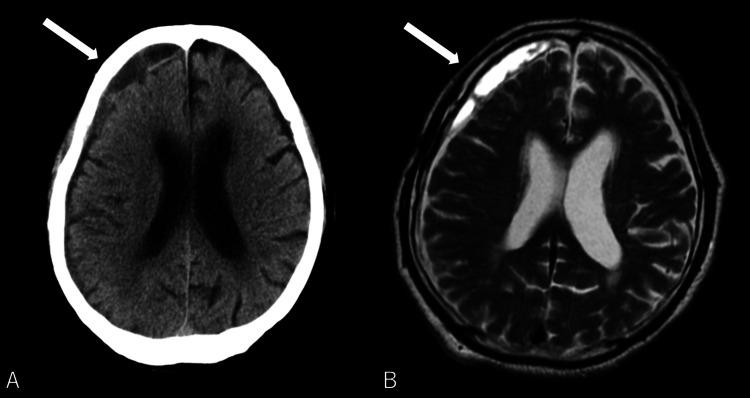

Traumatic herniations of the upper cervical spine are rare, with a higher likelihood of occurrence in older individuals. Their associated neurological symptoms can vary widely, often leading to delays in clinical diagnosis. We report the case of an 86-year-old man who developed neurological symptoms after a fall. Initially, intracranial pathology was suspected, and a head magnetic resonance imaging (MRI) revealed small chronic subdural hematomas, which were managed conservatively. However, as his paralysis progressed over the following days, a repeat brain CT showed no significant changes. Suspecting cervical spine involvement, further imaging identified a C2/3 disc herniation. The patient underwent emergency cervical laminoplasty, but postoperative subluxation required additional surgery, including C1-3 posterior fusion and C2/3 anterior fusion. Post-surgery, the patient exhibited improvement in paralysis affecting both the upper and lower extremities and a reduction in sensory deficits. Early diagnosis and treatment are crucial to improve neuropathic outcomes. A thorough understanding of the symptoms and characteristics of neurological damage to the upper cervical spine can significantly contribute to favorable results. Clinicians should be well-acquainted with this pathological condition.